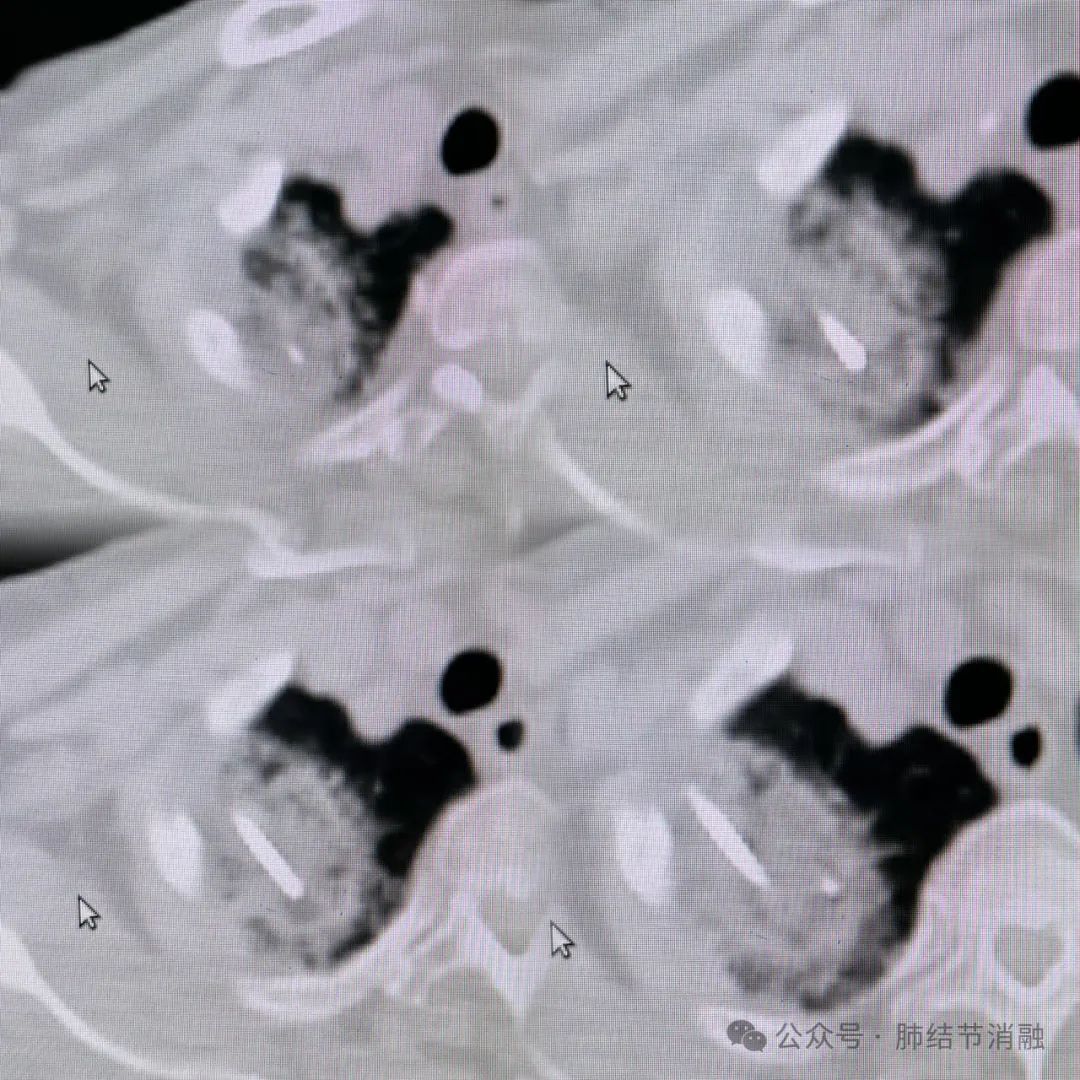

患者女性,86岁高龄,发现右肺尖磨玻璃结节6年余,逐渐长大,目前最大直径达3.1厘米,不耐受全麻手术,拟给予冷冻消融治疗。

患者术前CT图像